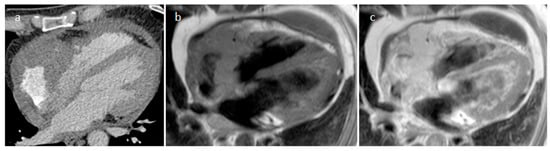

| Hematoma | Usually adulthood, previous surgery, traumatic heart injury, coagulopaty, anticoagulants | Pericardium | Usually, asymptomatic | Previous cardiac surgery, mass near surgical site or clips, usually well-defined borders. Usually absent contrast-enhancement | Acute phase: echo-lucent Chronic phase: mass like and echogenic | Heterogeneous, clips, hyperdense in acute phase, density decrease in chronic phase, calcific components in chronic hematoma | Acute: hyper T1w and T2w Subacute: heterogeneous with hyper T1 and T2w areas Chronic: hypo T1w and T2w with dark peripheral rim. No internal enhancement, possible rim enhancement |